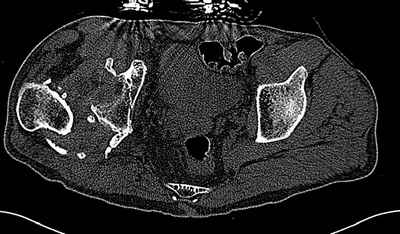

На последнем срезе КТ задний край практически отсутсвует по сравнения со здоровой стороной. Разумеется, что это плоскостное изображение, но головка вывихнулась не только в плоскостную щель захваченную на КТ. Если вы считаете, что удастся установить туда чашку даже низкопрофильную, остается пожелать вам успехов. Но перед этим можно смоделировать установку чашки на скиаграммах КТ.

За пожелание успехов - спасибо, думаю это пригодится, не очень понял про плоскостную щель, специально предоставил срезы на уровне свода - он цел, дефект заднего края ниже, за счет заглубления он будет еще меньше, по данным 3d - должно получиться.